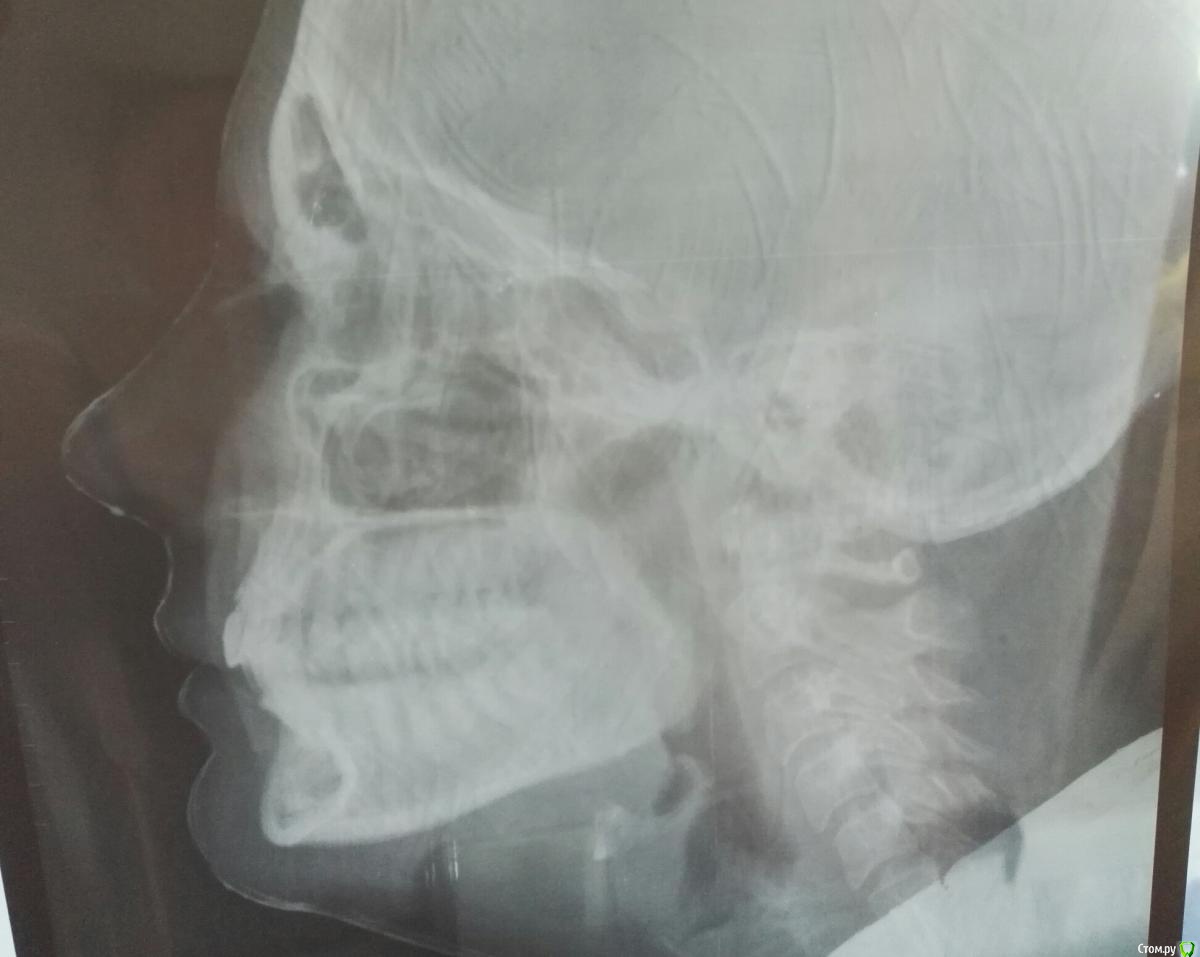

Izmailla Опубликовано 24 июля, 2017 Автор Поделиться Опубликовано 24 июля, 2017 (изменено) Прилагаю снимки, сделанные сегодня. Пожалуйста, подскажите, что думаете? Первый ортодонт, у которого я была говорит, что в бс нет смысла, центр поставить невозможно, при удалении четвёрки слева вч станет меньше, что повлечет удаление четвёрок на нч, а в результате все в общем будет плохо) Изменено 24 июля, 2017 пользователем Izmailla Ссылка на комментарий

Izmailla Опубликовано 24 июля, 2017 Автор Поделиться Опубликовано 24 июля, 2017 (изменено) Трг Изменено 24 июля, 2017 пользователем Izmailla Ссылка на комментарий